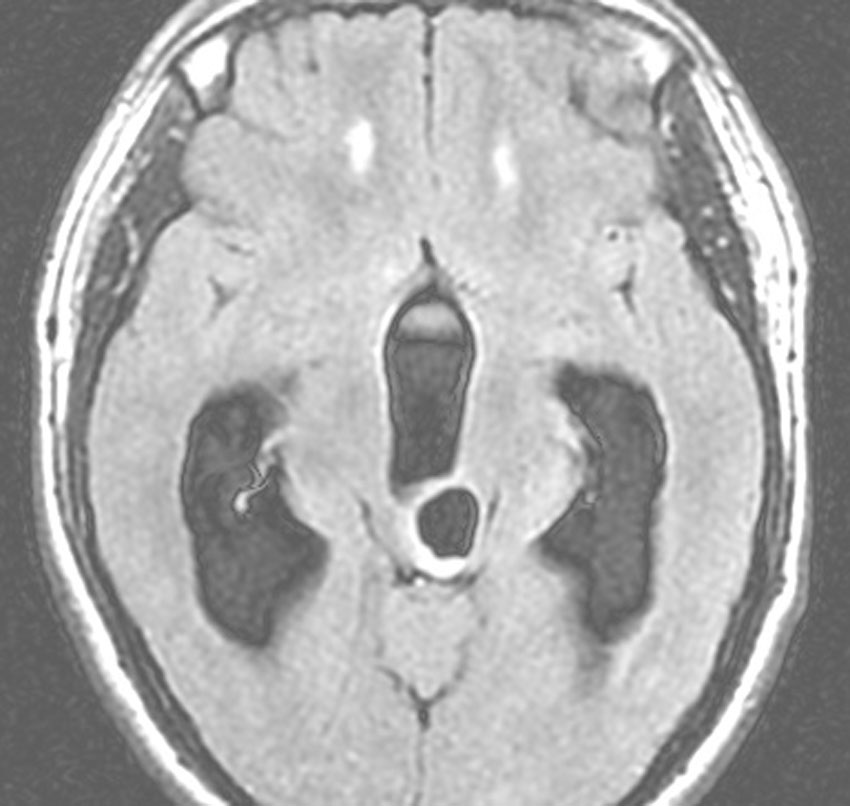

T2強調画像です。拡大した脳室の周囲に白くにじむような髄液のしみ出しがあります。脳室の周囲浮腫が出てくると頭痛や嘔吐が強くなります。